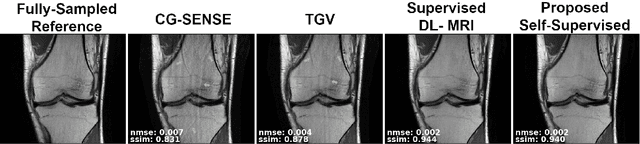

Abstract:Purpose: To develop an improved self-supervised learning strategy that efficiently uses the acquired data for training a physics-guided reconstruction network without a database of fully-sampled data. Methods: Currently self-supervised learning for physics-guided reconstruction networks splits acquired undersampled data into two disjoint sets, where one is used for data consistency (DC) in the unrolled network and the other to define the training loss. The proposed multi-mask self-supervised learning via data undersampling (SSDU) splits acquired measurements into multiple pairs of disjoint sets for each training sample, while using one of these sets for DC units and the other for defining loss, thereby more efficiently using the undersampled data. Multi-mask SSDU is applied on fully-sampled 3D knee and prospectively undersampled 3D brain MRI datasets, which are retrospectively subsampled to acceleration rate (R)=8, and compared to CG-SENSE and single-mask SSDU DL-MRI, as well as supervised DL-MRI when fully-sampled data is available. Results: Results on knee MRI show that the proposed multi-mask SSDU outperforms SSDU and performs closely with supervised DL-MRI, while significantly outperforming CG-SENSE. A clinical reader study further ranks the multi-mask SSDU higher than supervised DL-MRI in terms of SNR and aliasing artifacts. Results on brain MRI show that multi-mask SSDU achieves better reconstruction quality compared to SSDU and CG-SENSE. Reader study demonstrates that multi-mask SSDU at R=8 significantly improves reconstruction compared to single-mask SSDU at R=8, as well as CG-SENSE at R=2. Conclusion: The proposed multi-mask SSDU approach enables improved training of physics-guided neural networks without fully-sampled data, by enabling efficient use of the undersampled data with multiple masks.